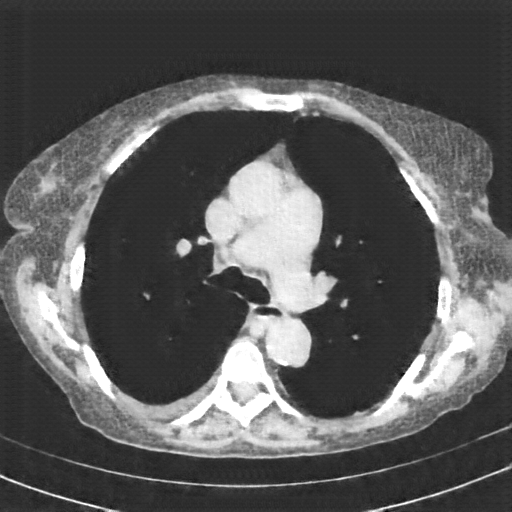

Original NATIVE CT scan (input)

Full window (WL 1023.5, WW 4095 β†’ Low βˆ’1024, High +3071)

Actual HU range: [-160.0, 240.0]